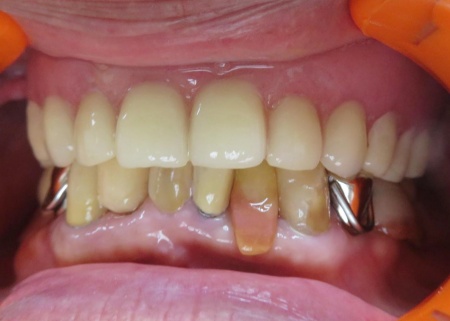

治療後

| 行ったご提案・治療内容 | 今回は、破損していたクラスプを新しく作り直し、入れ歯を修理する方法を提案しました。 これまでも同様の修理を行っているため、患者さまも修理の流れをよく理解されています。 入れ歯を修理する場合は、入れ歯をお預かりして数日から1週間ほどお時間をいただくのが一般的ですが、当院では歯科医師が院内でクラスプを作製できるため、約1時間で修理をすることが可能です。 ただ長期的な使用状況によっては、再度調整や修理が必要になることもあります。 修理方法のメリットとデメリットをお伝えし、同意いただきました。 まずは入れ歯を装着した状態で型取りを行い、模型を作製します。 完成した模型に入れ歯を装着し、クラスプを固定する場所を削りました。 クラスプ用のワイヤーは手作業で曲げながら、残っている歯の形態や傾きに合わせて精密に調整します。 その後、完成したクラスプを入れ歯に取り付けたうえで装着していただき、実際にお口の中で安定性や装着感を確認しました。 最後に、噛み合わせや着脱のしやすさ、見た目に問題がないかなどを確認し、治療を終了しています。 |